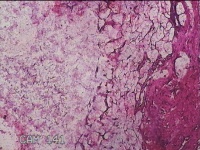

右拇指肿物

性别

女

年龄

23岁

临床诊断

1.右拇指肿物性质待查? 2.腱鞘巨细胞瘤

一般病史

发现右拇指肿块7月余。

标本名称

大体所见

灰白粉红色肿物2x1.5x0.8cm一个,表面光滑,肿物表面有少许脂肪,切开肿物呈实性,切面灰白粉红色,质中。